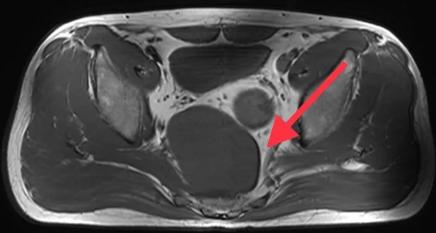

近日,余先生行色匆匆地来到同济大学附属东方医院胃肠肛肠外科傅传刚教授特需就诊,他自述自己既没有排便习惯的改变,身体也没有其它不舒服,但就是10天前在外院做B超检查时发现盆腔低回声,此外MR检查提示骶前直肠后可见一等T1,混T2回声,大小50*72*91mm肿物,结肠镜提示可见腔外压迫。余先生为此感到焦虑,难道自己得的是癌症?还是什么其他的疾病?他思虑万千,恳求傅传刚教授一定要帮他查出自己到底患了什么疾病!

傅传刚教授给余先生安排进行了详细查体和辅助检测。查体发现肛门外形正常,直肠指诊后壁齿线上约3cm向上可触及巨大肿物下缘,粘膜完整。盆腔(MRI增强)显示盆底占位,考虑神经源性肿瘤可能。